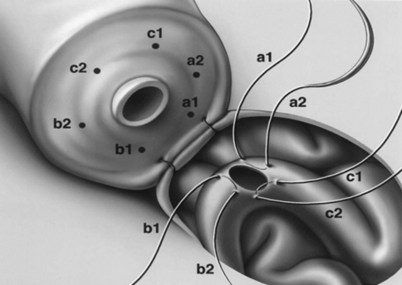

This method, originally described as the triangulation technique, was introduced by Berger (1998). There are several advantages of the methods over previous techniques (see Table 22–3) (Goldstein, 1999). The setup is identical to that for the classical end-to-side vasoepididymostomy. After the vas is fixed to the opening in the epididymal tunica, six microdots are placed on the cut surface of the vas in an identical fashion to that described for vasovasostomy. The epididymal tubule selected is dissected with blunt microscissors and the micro needle holder until it is free of surrounding tissue and prominent. The tubule is then stained with indigo carmine. Using 10-0 monofilament nylon sutures approximately 2 inches in length, double armed with 70-µm diameter fish hook–shaped tapered needles, three sutures are placed in the epididymal tubule in a triangulation fashion. The apex of the triangle faces the inferior edge of the vasal mucosa. The needles are not pulled through but left in situ, creating a triangle of needles (Fig. 22–35). Using a 15-degree microknife with the blade pointing upward, a generous opening is made in the epididymal tubule in the center of the triangle created by the three needles (Fig. 22–36).

The three needles are then pulled through. The six needles are now laid out so as to avoid a spaghetti-like tangle. A glass slide is touched to the fluid exuding from the opening in the epididymal tubule and mixed with human tubal fluid media, covered with a coverslip, and examined by the surgeon using the separate bench microscope under 400-power magnification. If sperm are present (whether motile or not), the decision is made to proceed with the anastomosis. Sperm are aspirated into micropipets first (Fig. 22–37) and expressed into human tubal fluid media and sent for cryopreservation if motility is observed. Sperm that initially appear immotile, when mixed with human tubule fluid, often regain motility adequate for successful cryopreservation. Even immotile sperm should be placed in the media and evaluated for potential cryopreservation. If the needles are pulled through before placing the microsurgical sutures or before making an opening in the epididymal tubule, epididymal fluid and sperm would immediately leak through the suture hole, causing the tubule to collapse. This makes placement of subsequent sutures and creation of the opening in the tubule considerably more difficult. Leaving the needles in the epididymal tubule before making the opening also prevents accidental cutting of the sutures when making the opening in the center of the triangle. After abundant sperm have been aspirated into micropipets and cryopreserved, the six needles are passed inside out the vas deferens exiting through the six previously placed microdots in the order indicated (Fig. 22–38). Each pair of sutures is then sequentially tied beginning with suture a1 and a2, then b1 and b2, and finally c1 and c2. Tying of these sutures intussuscepts the epididymal tubule into the vas lumen (Fig. 22–39). This creates a water-tight closure (Fig. 22–40). In addition, the flow of epididymal fluid from the epididymal tubule into the vas deferens tends to plaster the edges of the epididymal tubule against the mucosal walls of the vas deferens, further helping create a leakproof closure. The second layer of the anastomosis is completed in an identical fashion to that described for the classical end-to-side operation described earlier (Fig. 22–41A and B).

For anastomoses to small epididymal tubules such as those found in the caput or to the efferent ductules (Chan et al, 2005), the three-stitch triangulation technique may be impossible. We now employ a two-stitch longitudinal intussusception technique for all vasoepididymostomies. It is much easier to perform and is even more successful. With this method, four microdots are marked on the cut surface of the vas deferens and two parallel sutures are placed in the distended epididymal tubule longitudinally, but not pulled through (Fig. 22–42A and B). Marmar suggests mounting two needles in the needle holder and placing them simultaneously transversely in the tubule. However, if the needles are not pulled through to avoid leakage of fluid and tubular collapse, they can be placed one at a time with greater control and accuracy (Chan et al, 2005; Schiff et al, 2005). Using a 15-degree microknife, an opening is made exactly between and parallel to the two previously placed sutures. Of note, we have also developed a single-arm technique of vasoepididymostomy, which is almost as effective as the double-arm technique (Fig. 22–43) (Monoski et al, 2007). This technique is valuable when double-armed sutures are not available.